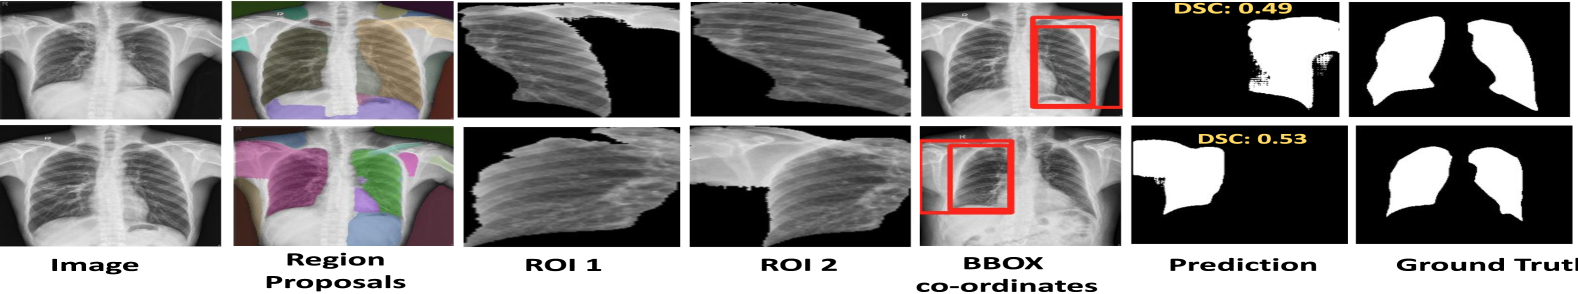

6.1 Limitations

In this section, we highlight the limitations of our method. We report the limitations both at SAM and CLIP levels as shown in  Fig. 9. The first row shows the case multiple mask generations by SAM leads to the misclassification of ROIs by CLIP. Specifically, CLIP erroneously predicts the SAM region mask for the lungs, thereby impacting the final prediction. The second row shows the case where SAM correctly generates masks for both ROIs, however, CLIP misclassifies the crop for the left lung. The third and fourth rows illustrate scenarios where SAM fails to predict the ROI for the left lung, consequently leading to CLIP retrieving the incorrect crop region.

Figure 9: Visualization of failure cases on X-ray labels and masks dataset [19]. First two rows: SAM generates masks for both the left and right lung, but CLIP retrieves only the right lung mask correctly. While rows three and four show cases where SAM does not generate a mask for the left lung, eventually CLIP does not recognize the correct crop for the left lung in such cases.